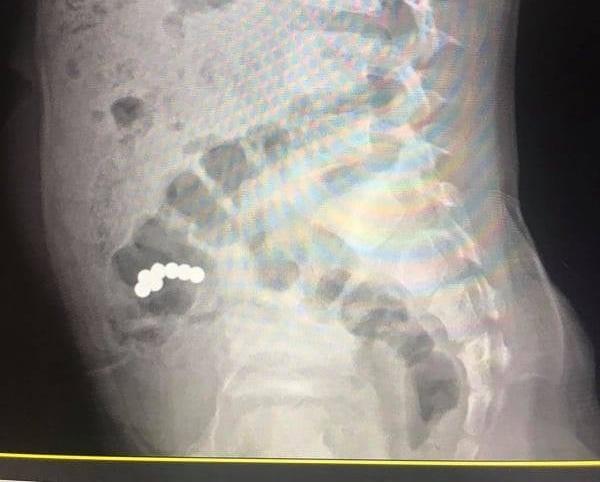

На Прикарпатті хлопчик проковтнув магнітні кульки - дитині зробили операцію

В більшості випадків небезпеку можна попередити, кажуть в лікарні.